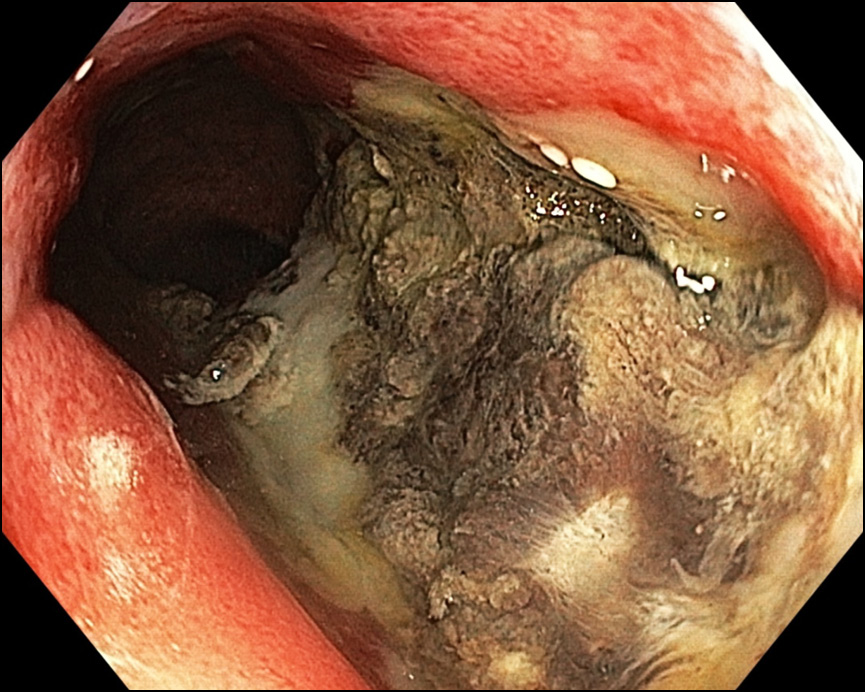

Рис. 1. Фиброколоноскопия от 21.11.2019: ангиэктазии в нижнеампулярном отделе прямой кишки

При фиброколоноскопии от 21.11.2019 в нижнеампулярном отделе прямой кишки по всем стенкам определяются ангиэктазии (рис. 1), слизистая контактно ранима. Внутренние геморроидальные узлы увеличены, не тромбированы.